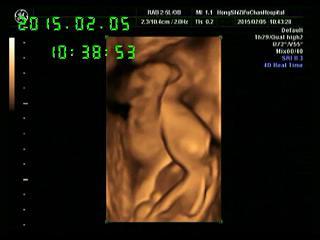

27周做的四维彩超,医院给刻盘了,这是一张截图,孩子的两腿翘着呢,请问能看出性别吗? 点击展开 匿名用户 2015-02-09 09:52 为您推荐: 其他回答 你现在是孕中期了,这时彩超单不能看出胎儿性别。建议你定期检查胎儿的健康状况即可。 一缕阳光花开艳 2015-02-09 10:57 相关问题 刻盘归来,发四维彩超照,能看出性别吗 上海四维彩超最便宜多少钱呀?可以刻盘吗?在哪里? 有宝妈在济南456做四维彩超的吗?现在多钱了?需要预约吗?是不是拍照刻盘?谢谢!